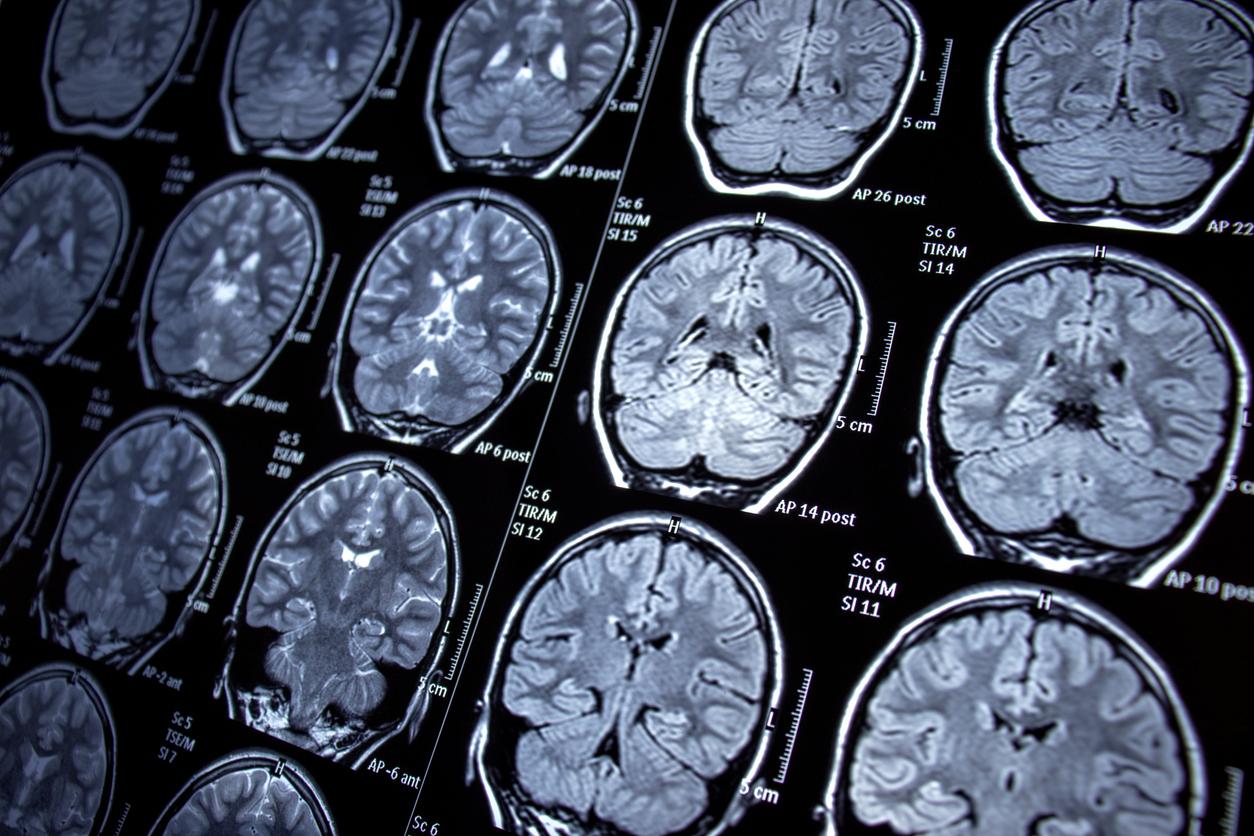

Dans le cadre de ces travaux, les auteurs ont recruté 165 personnes en bonne santé et 227 adultes ayant souffert d’une tumeur cérébrale ou d’un accident vasculaire cérébral dans des parties spécifiques du cerveau. Les scientifiques ont ensuite introduit une nouvelle approche de "cartographie des lésions-déficits" pour analyser et comprendre les schémas complexes des formes courantes de lésions cérébrales.

"Ils ont étudié les associations entre les régions du cerveau comme un réseau mathématique dont les connexions décrivent la tendance des régions à être affectées ensemble, soit à cause du processus pathologique, soit en raison d'une capacité cognitive commune", peut-on lire dans un communiqué.

Grâce à leur approche, les chercheurs sont parvenus à déterminer quels patients réussissaient moins bien les tâches nécessitant l'intelligence fluide en fonction de leurs lésions. D’après les résultats, les troubles de l'intelligence fluide touchaient essentiellement les adultes présentant des lésions frontales droites. "Nos résultats indiquent pour la première fois que les régions frontales droites du cerveau sont essentielles aux fonctions de haut niveau impliquées dans l'intelligence fluide, comme la résolution de problèmes et le raisonnement", a déclaré Lisa Cipolotti, auteure de l’étude.